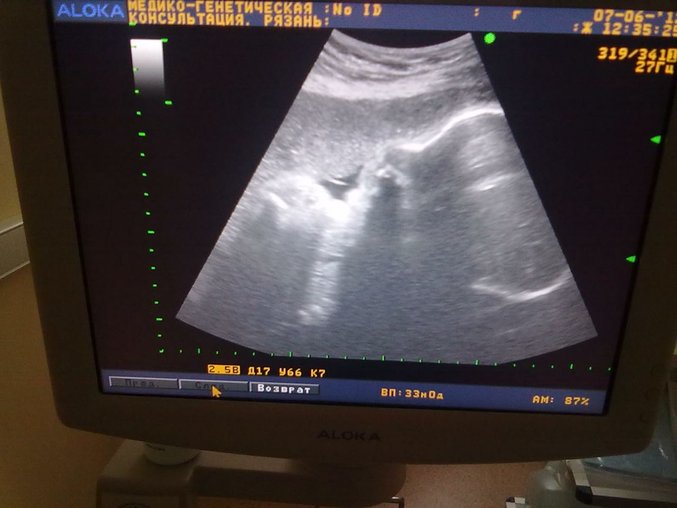

тут 33 недели - Илюша позевал